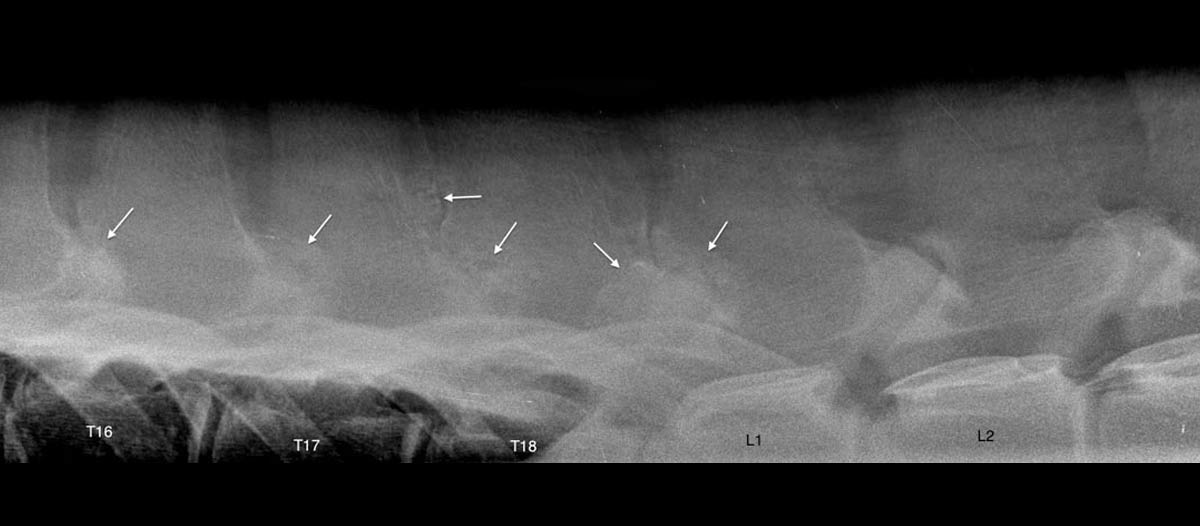

La radiographie est une technique ancienne qui connaît encore une grande évolution dans notre monde digital moderne. EquiSound dispose de 2 systèmes de radiographie digitale combinés à une machine à rayons X puissante de 80.000 Watts (80 kV). Nous pouvons produire des radiographies du cheval complet d’excellente qualité, tête, encolure et dos inclus.